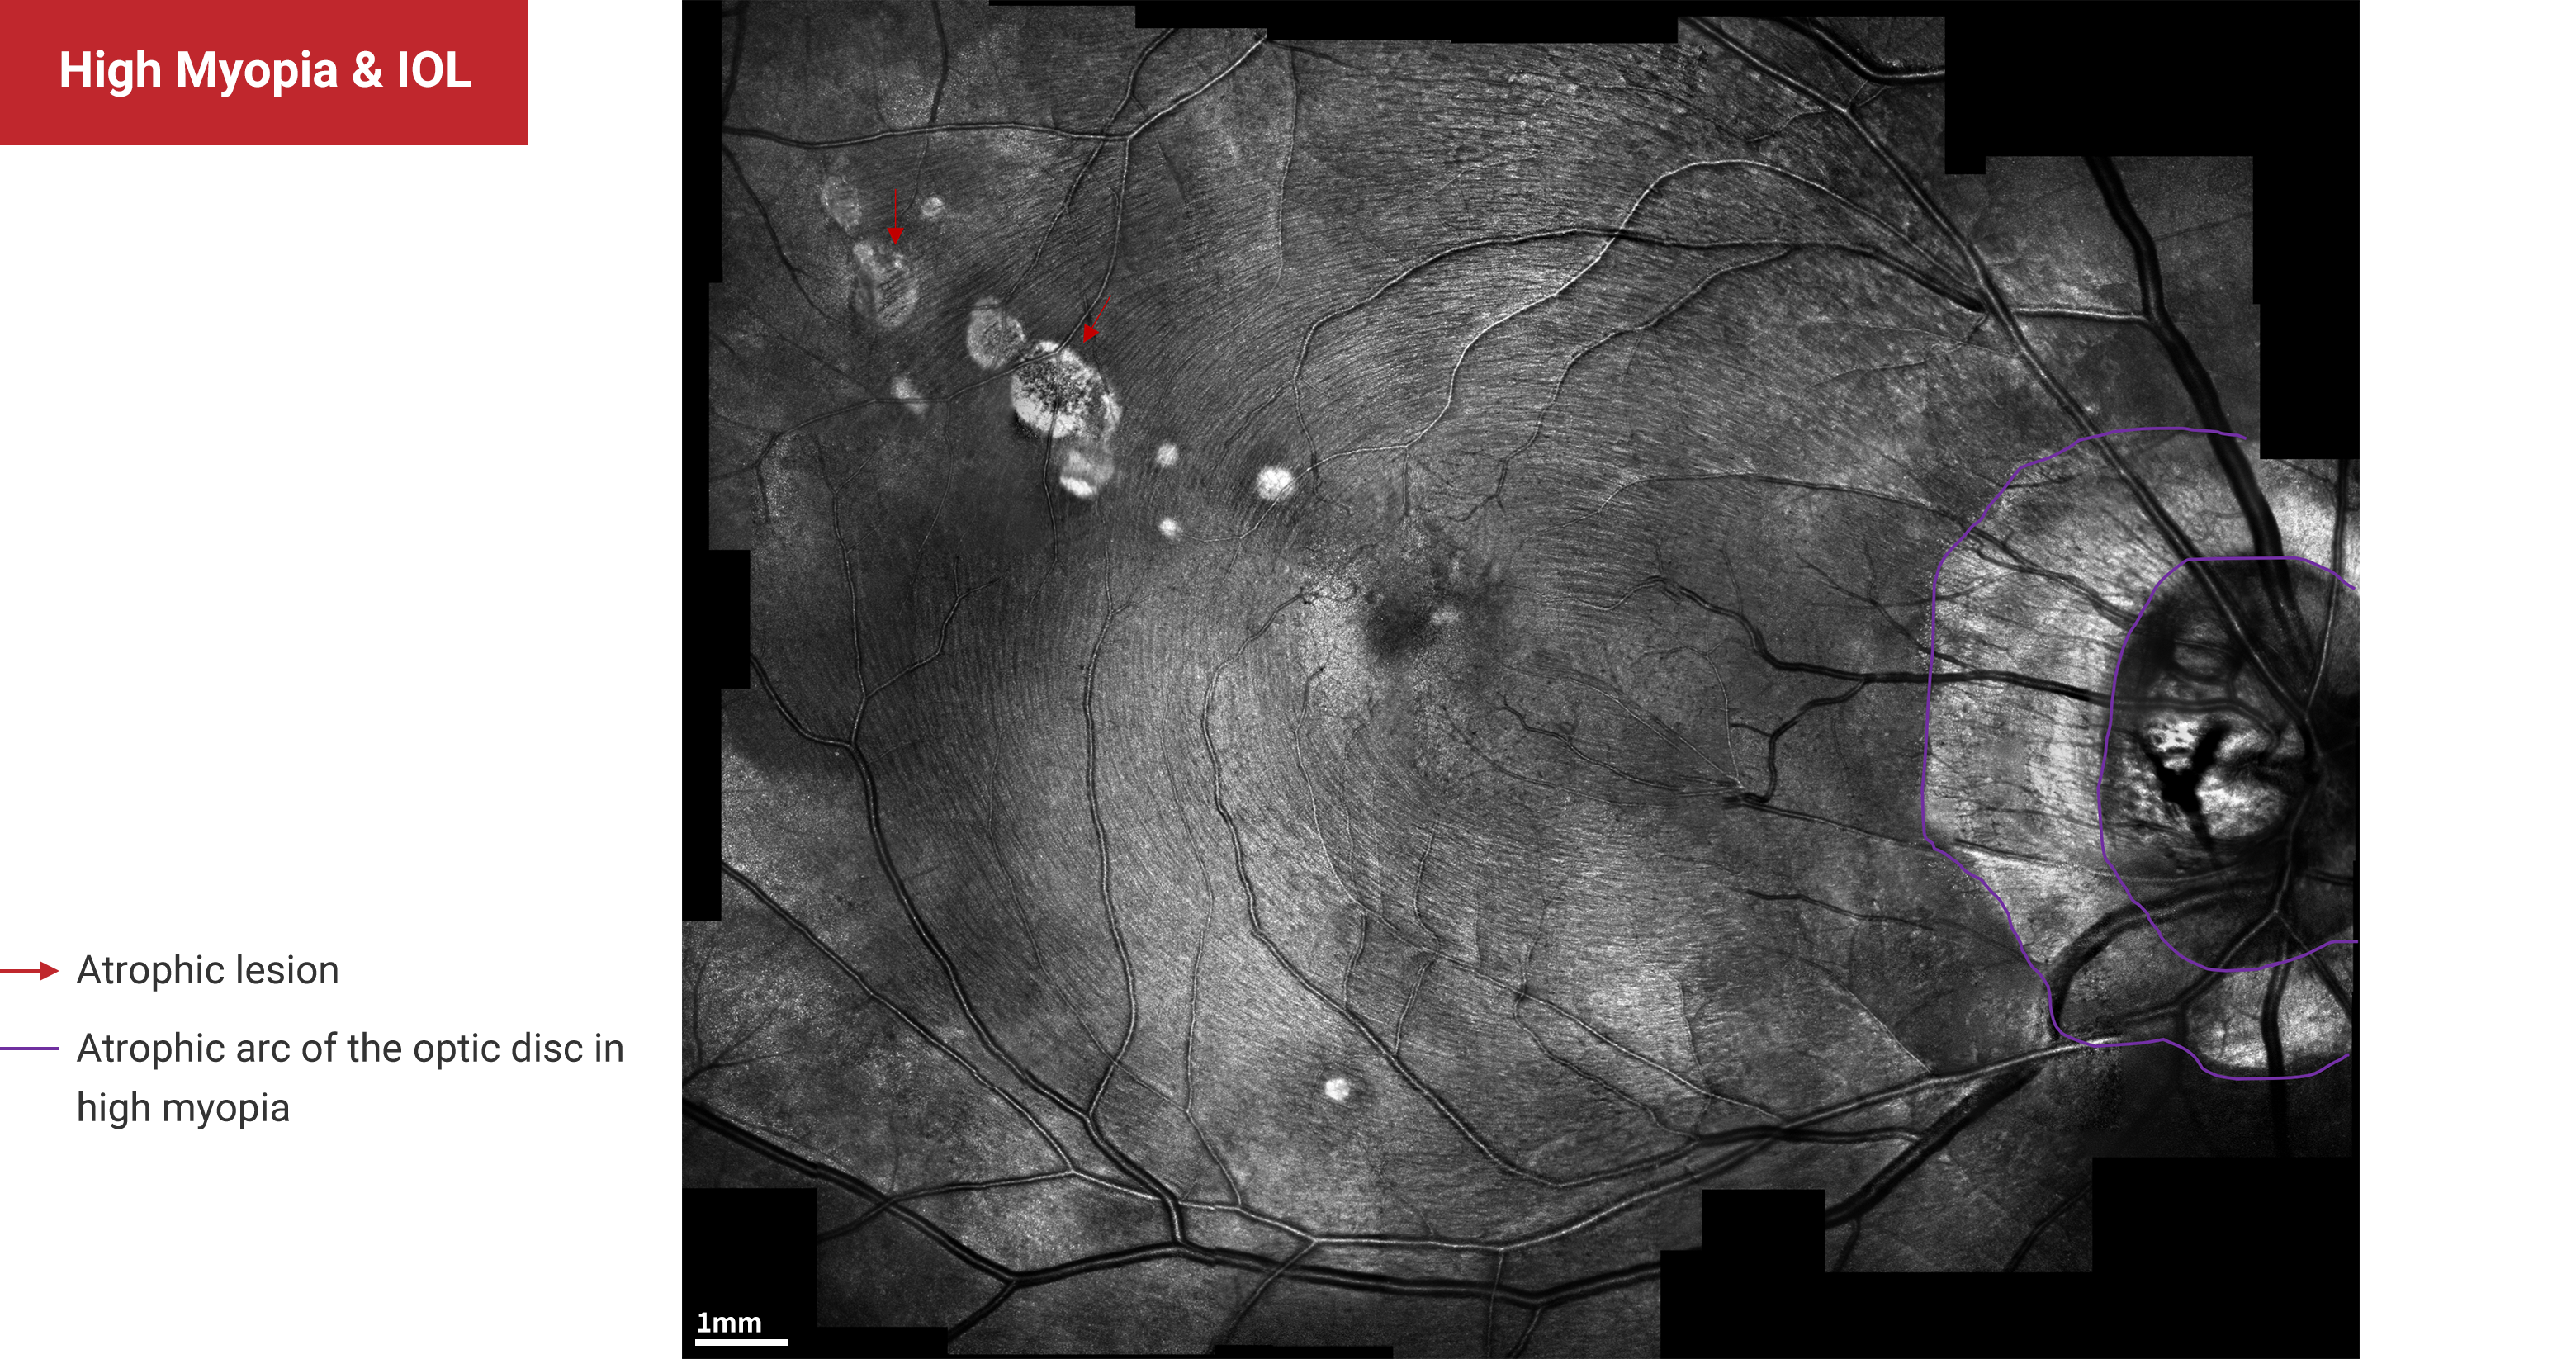

High Myopia & IOL